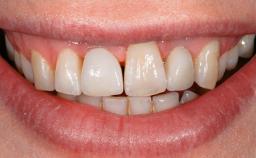

A 73-year-old woman was referred to the Division of Periodontology (University of Geneva School of Dental Medicine) after repeated unsuccessful treatment of a peri-implant infection. She was systemically healthy and did not smoke. The patient’s history revealed that, three years earlier, an immediate implant (Straumann Tapered Effect RN 4.8/4.1; Institut Straumann AG, Basel, Switzerland) had been inserted to replace the upper right central incisor. A metal-ceramic crown had been delivered using an adhesive resin cement. One year later, the patient had consulted another dentist due to discomfort in the soft tissues in the implant region. There was a suppurating peri-implant pocket, 10 mm deep. Peri-implant bone loss and excess luting cement were seen on the radiograph. The situation was treated with non-surgical debridement, amoxicillin, and repeated submucosal irrigation with a chlorhexidine digluconate solution. The patient was referred after the suppuration had persisted for several months.

Lip Line No exposure of papillae Exposure of papillae Full exposure of mucosa margin

Periodontal Phenotype Low-scalloped, thick Medium-scalloped, medium-thick High-scalloped, thin